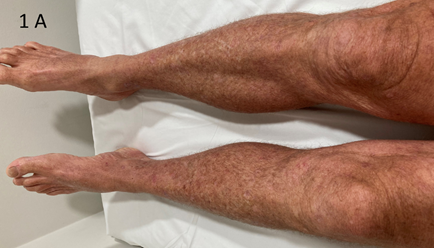

Examination revealed circumferential involvement of both lower legs, worse anteriorly, consistent with sun exposure. The field change extended onto the proximal dorsum of both feet. There were no active KCs in the leg fields. (Figure 1) The rationale, process, and side effects of VMAT for ESFC of both legs was explained and he consented to treatment and proceed to planning. Prior to planning he was reviewed by a lymphoedema physiotherapist and was prescribed compression therapy consisting of below knee flat knit compression stockings and compression wrap garments. The plan was for him to wear these from the beginning of therapy except at night. The garments cost $AUD 500 per leg.

Figure 1A A – Lower legs at presentation – anterior view.

Figure 1 Lower legs at presentation.